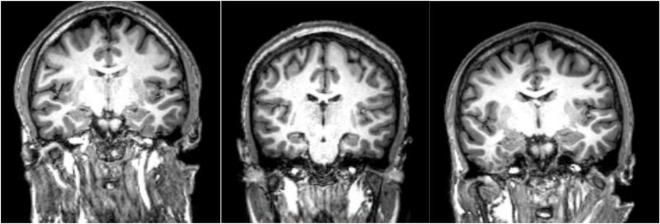

In this review article we have consolidated the imaging literature of patients with schizophrenia across the full spectrum of modalities in radiology including computed tomography (CT), morphologic magnetic resonance imaging (MRI), functional magnetic resonance imaging (fMRI), magnetic resonance spectroscopy (MRS), positron emission tomography (PET), and magnetoencephalography (MEG). We look at the impact of various subtypes of schizophrenia on imaging findings and the changes that occur with medical and transcranial magnetic stimulation (TMS) therapy. Our goal was a comprehensive multimodality summary of the findings of state-of-the-art imaging in untreated and treated patients with schizophrenia. Clinical imaging in schizophrenia is used to exclude structural lesions which may produce symptoms that may mimic those of patients with schizophrenia. Nonetheless one finds global volume loss in the brains of patients with schizophrenia with associated increased cerebrospinal fluid (CSF) volume and decreased gray matter volume. These features may be influenced by the duration of disease and or medication use. For functional studies, be they fluorodeoxyglucose positron emission tomography (FDG PET), rs-fMRI, task-based fMRI, diffusion tensor imaging (DTI) or MEG there generally is hypoactivation and disconnection between brain regions. However, these findings may vary depending upon the negative or positive symptomatology manifested in the patients. MR spectroscopy generally shows low -acetylaspartate from neuronal loss and low glutamine (a neuroexcitatory marker) but glutathione may be elevated, particularly in non-treatment responders. The literature in schizophrenia is difficult to evaluate because age, gender, symptomatology, comorbidities, therapy use, disease duration, substance abuse, and coexisting other psychiatric disorders have not been adequately controlled for, even in large studies and meta-analyses.

在这篇综述文章中,我们整合了精神分裂症患者在放射学全模态范围内的影像学文献,包括计算机断层扫描(CT)、形态学磁共振成像(MRI)、功能磁共振成像(fMRI)、磁共振波谱(MRS)、正电子发射断层扫描(PET)和脑磁图(MEG)。我们研究了精神分裂症的各种亚型对影像学结果的影响,以及药物治疗和经颅磁刺激(TMS)治疗所带来的变化。我们的目标是对未经治疗和经治疗的精神分裂症患者的最新影像学研究结果进行全面的多模态总结。精神分裂症的临床影像学检查用于排除可能产生类似精神分裂症患者症状的结构性病变。尽管如此,人们发现精神分裂症患者的大脑存在整体体积缩小,伴有脑脊液(CSF)体积增加和灰质体积减少。这些特征可能会受到疾病持续时间和/或药物使用的影响。对于功能研究,无论是氟脱氧葡萄糖正电子发射断层扫描(FDG PET)、静息态功能磁共振成像(rs-fMRI)、任务态功能磁共振成像(task-based fMRI)、扩散张量成像(DTI)还是脑磁图(MEG),大脑区域之间通常存在激活不足和连接中断的情况。然而,这些结果可能会因患者表现出的阴性或阳性症状而有所不同。磁共振波谱通常显示由于神经元丢失导致的低N-乙酰天门冬氨酸和低谷氨酰胺(一种神经兴奋性标志物),但谷胱甘肽可能会升高,尤其是在治疗无反应者中。精神分裂症的文献很难评估,因为即使在大型研究和荟萃分析中,年龄、性别、症状、合并症、治疗使用情况、疾病持续时间、药物滥用以及其他并存的精神障碍等因素也没有得到充分控制。